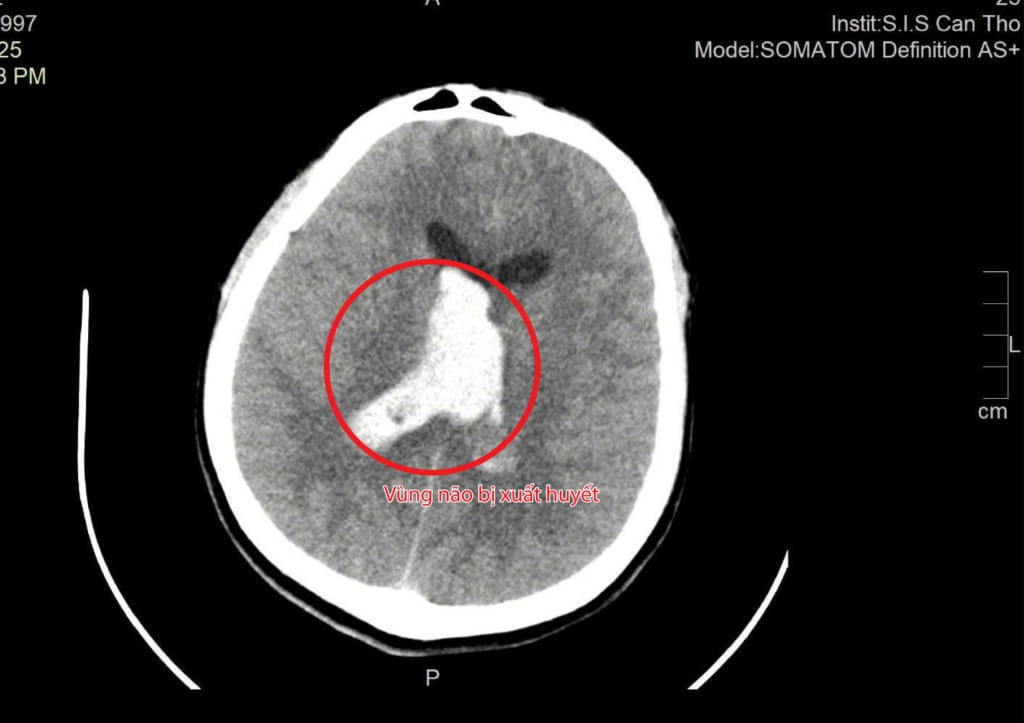

Tổn thương chảy máu não trên phim chụp - Ảnh BVCC

BS Tôn Nữ Thị Điểm, khoa Ngoại tổng hợp chia sẻ: Sau khi tiếp nhận và cho chụp CT não, chúng tôi phát hiện bệnh nhân bị xuất huyết trong não và não thất, kèm phù não nặng. Nếu không được phẫu thuật kịp thời, áp lực nội sọ sẽ tăng nhanh, có thể đe dọa tính mạng.